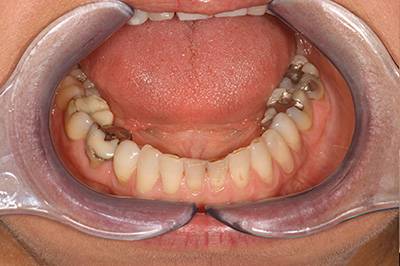

10. eset

Savas kémhatású anyagok, mint például a szénsavas üdítők túlzott használata is a fogak zománcrétegének nagyfokú károsodását okozhatják. 35 éves férfi páciensnek készítettünk a frontfogaira Zirkon koronákat, a rágófogaira pedig fémkerámia szóló koronákat. 28 koronával állítottuk helyre a fogazatot.